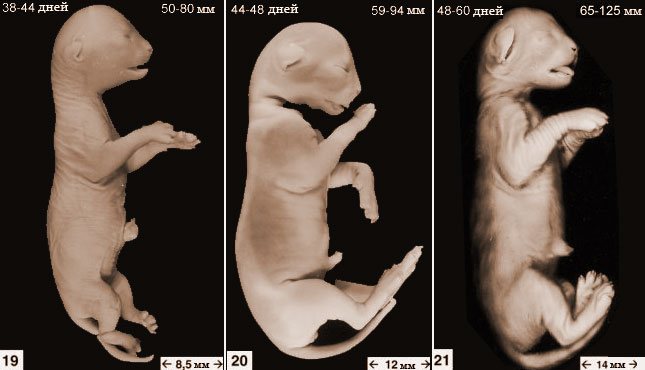

Развитие плода, стадии чаще всего обозначаются в неделях, а на ранних сроках используются дни. Ниже более подробно рассматривается внутриутробное развитие с самых первых дней.

Четвертая неделя (22-28 дней)

Плодное яйцо увеличивается до размера 15-20 мм. В данный момент эмбрион кошки с трудом отличается от других млекопитающих. Начинается постепенное развитие внутренних органов, в том числе мозга и сердца.

К концу 28 дня у малыша начинают формироваться лапки, подушечки, коготки. Поведение кошки в этот период не меняется. Возможно появление токсикоза.

Пятая-шестая неделя (29-42 дня)

На 5-6 неделе постепенно формируются органы чувств. Как известно, у кошачьих хорошо развиты слух и чувство равновесия. Также на этом этапе происходит постепенная подготовка к отращиванию усов, появляются еще мягкие когти.

Седьмая-восьмая неделя (43-56 дней)

На рентгене хорошо просматриваются кости и позвоночник. Шерсть уже полностью сформирована. В целом на 50-й день котята уже готовы к рождению, но данный момент также зависит от породы.

Развитый плод